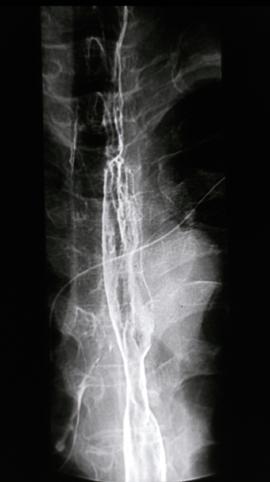

Criteria of Hist.ClassificationMalignant epithelial tumor/Undifferentiated carcinoma

LocationEsophagus/More than one of the above

Technique, MethodX-ray

Macroscopic TypesType 5 Unclassfied type/

Size40 -